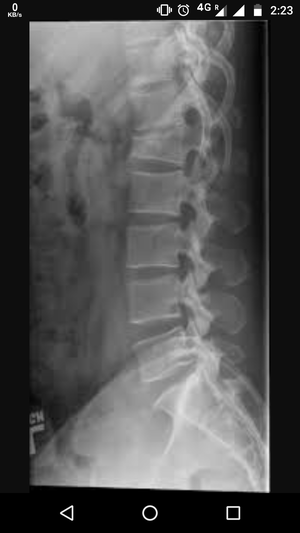

Diagnosis???